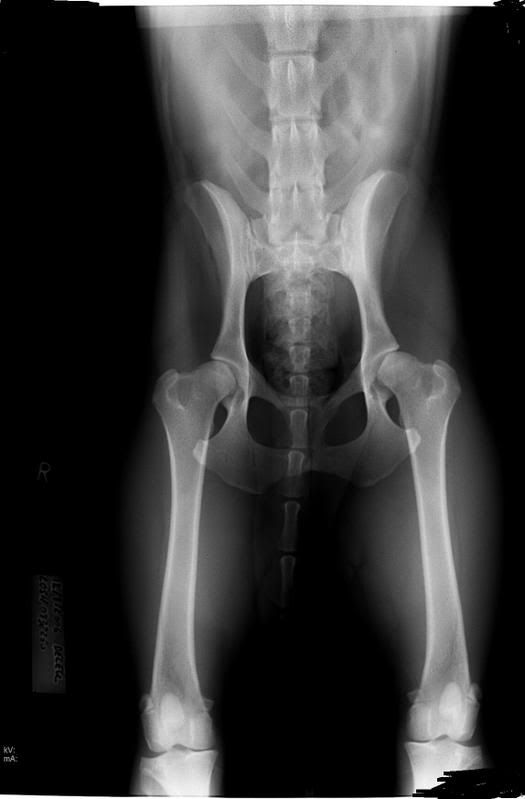

- ten eerste wordt er in mijn ogen heel vaak kortzichtig gereageerd op het onderwerp HD : HD heeft maar een erfelijkheidsgraad van 30%, dat wil dus zeggen dat 70% van de honden die HD hebben deze langs niet erfelijke weg gekregen hebben.

- ten derde is het nog steeds zo dat de strengheid van beoordelen verschillend is per land : tot voor twee jaar moest een hond hier (in belgië) zo goed als gouden heupjes hebben om een A te krijgen. wat in één land een A is kan in een ander een B zijn en in een derde een C.

sette heeft dus een HD-C vader en die is heel bewust uitgekozen om zijn prachtige kwaliteiten, uiterlijk maar vooral ook karakter. en guess what : sette hééft gouden heupjes, beoordeeld in die zeer strenge periode kreeg ze een A.

ik snap Inge haar mening, maar ik vind het ook lastig, in hoeverre weet of kan men bewijzen dat de HD-C/D niet erfelijk is? net zo min als dat je niet altijd weet of het puur erfelijk is, maar door verkeerd opgroeien, voer enz? ( hoewel ik het dan wel weer eens ben met rosita... als de aanleg ervoor hebben er niet is, dan denk ik dat een hond niet zomaar door voer , beweging enz Hd ontwikkeld.. dus toch erfelijk, iig de aanleg)